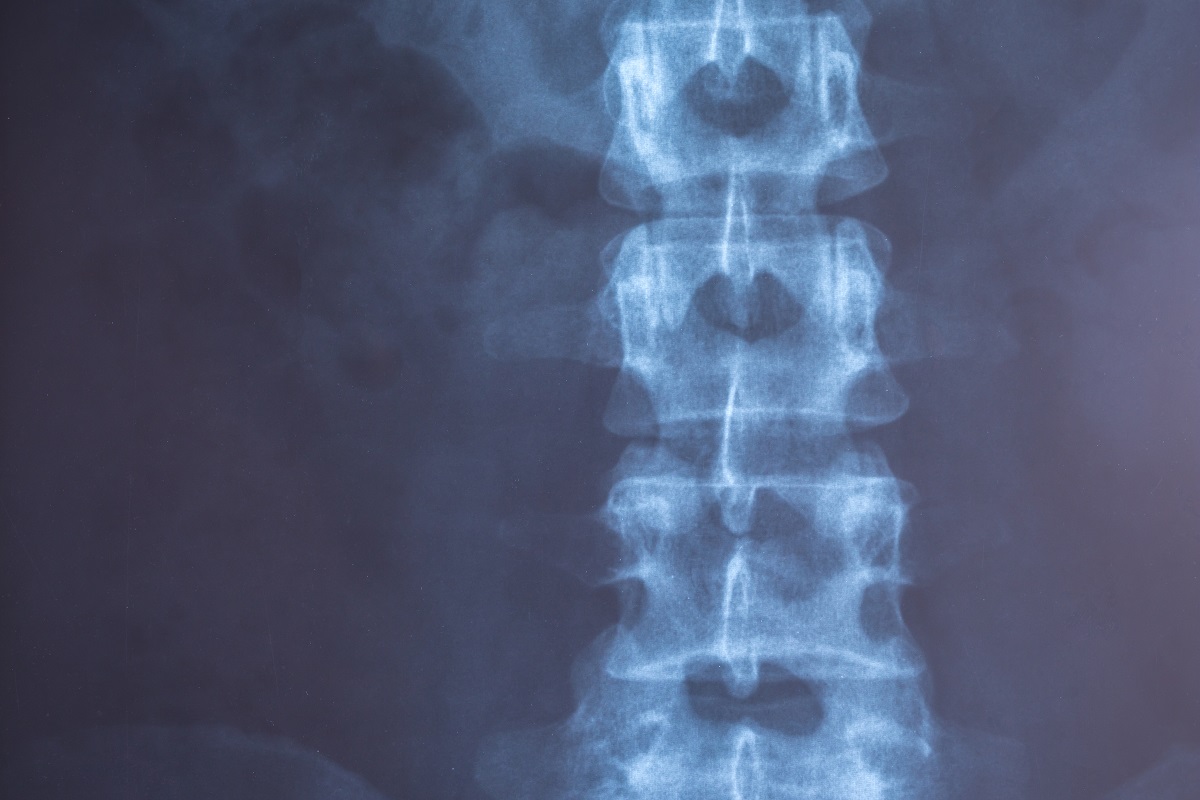

Позвоночный столб представляет собой основную часть человеческого скелета. Хребет состоит из позвонков, между которыми расположены пульпозное (гелеобразное) ядро и плотное фиброзное кольцо по краям (межпозвонковые диски). Они выполняют защитную функцию, оберегая структуры позвоночника от возможных повреждений при физической активности. При ББ происходит окостенение и сращение эластичных элементов, потеря подвижности. Наблюдается замещение костной тканью.

Специалисты различают три стадии болезни Бехтерева:

1. Дорентгенологическая (ранняя). На рентгеновских снимках отсутствуют признаки повреждения КПС, хребта. На МРТ заметны проявления сакроилеита.

2. Развернутая. Врач видит на рентгеновском снимке сакроилеит. Не выявляются специфические изменения в позвоночной оси.

3. Поздняя. На рентгенограмме определяются очаги сращения костных элементов.

Инструментальные методы исследования включают рентгенографию позвоночной оси, крестца. Специалист внимательно изучает снимки, обращая внимание на крестцово-подвздошную область. При первой стадии проявляется нечеткость контуров сустава. Наличие эрозивных дефектов свидетельствует о второй стадии. При третьей стадии отмечается неполное сращение эластичных структур, при четвертой — полное.